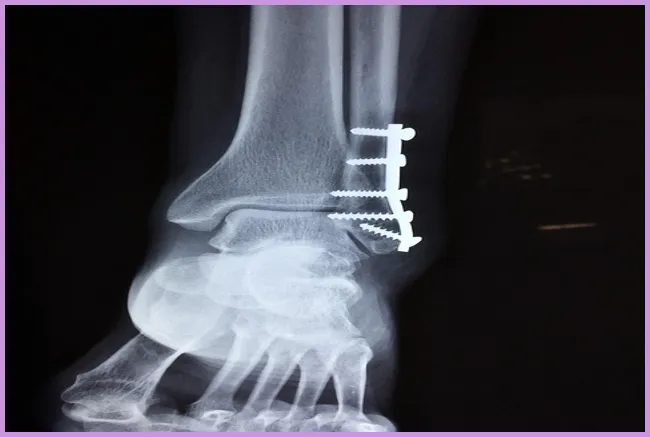

- 외상: 넘어지거나 부딪히는 등의 외상으로 인한 손상이 고관절 통증의 주원인 중 하나입니다.